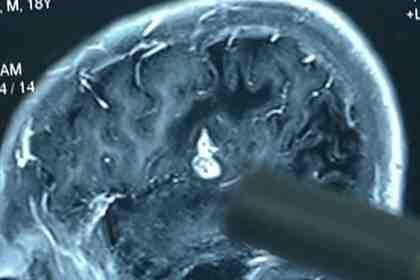

Из мозга китайца достали живого червя длиной почти в 13 сантиметров. Паразит жил в голове мужчины 17 лет, пишет Daily Mail.

23-летний молодой человек рассказал, что с шести лет страдал онемением конечностей. За медицинской помощью он обратился лишь тогда, когда окончательно утратил чувствительность в правой верхней части туловища.